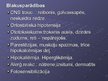

Diurētiskie līdzekļi

Diurētiskie līdzekļi

Diurētiskie līdzekļi